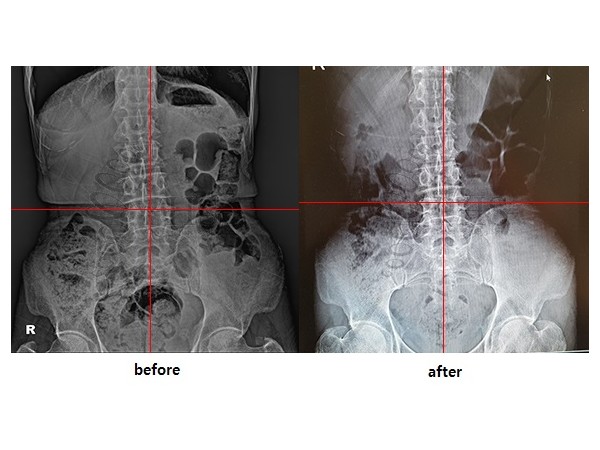

교정사례

PHS효과?